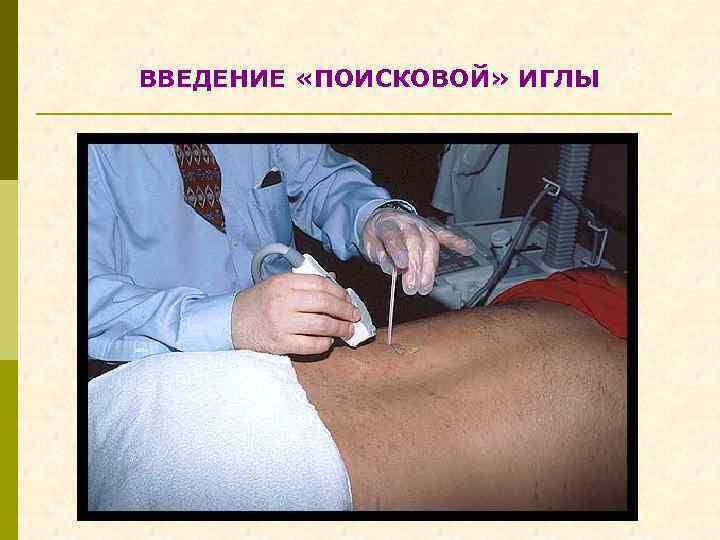

ВВЕДЕНИЕ «ПОИСКОВОЙ» ИГЛЫ